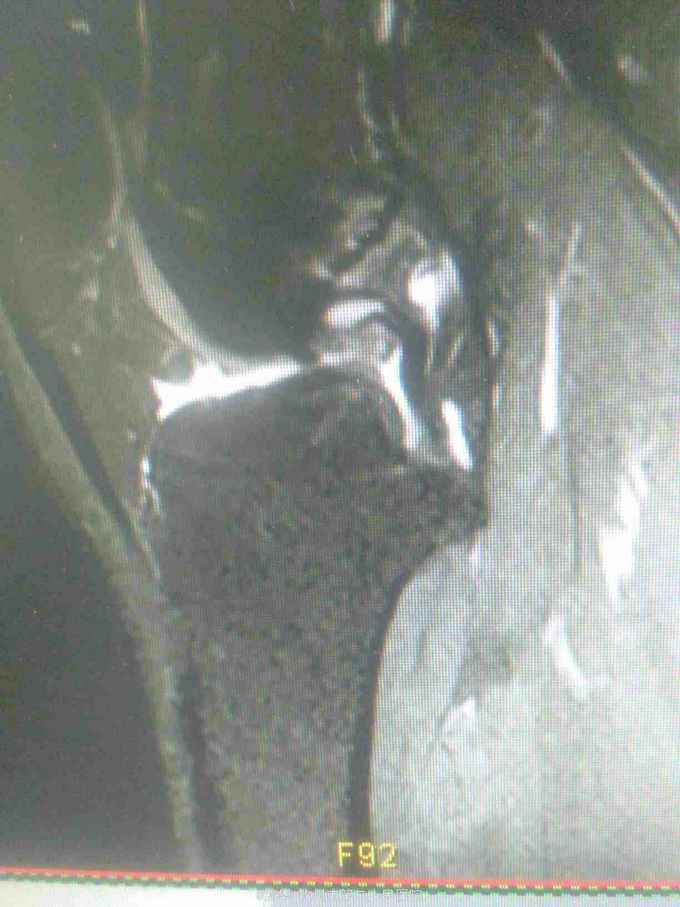

主诉:扭伤致左膝关节活动受限3月余。病史:患者男性,31岁,于入院3月余前扭伤左膝关节,致左膝关节肿痛、活动受限,尚可站立行走,但不能剧烈运动及重体力劳动,曾行磁共振检查提示左膝前交叉韧带损伤,半月板损伤,现为进上一步治疗入院。

查体:左膝关节无明显压痛,前抽屉试验阳性,侧方应力试验、麦氏征、研磨试验均阴性,膝关节屈伸活动可,余查体未见特殊。 辅查:膝关节磁共振提示左前交叉韧带损伤,左膝关节半月板损伤。

诊断:左膝关节前交叉韧带断裂,左膝关节半月板损伤。 治疗:予硬外麻下行左膝关节前交叉韧带重建术。